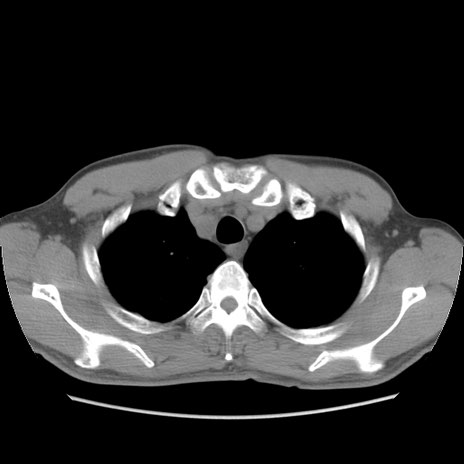

症例56 CT(横断像)

脂肪ウインドウ